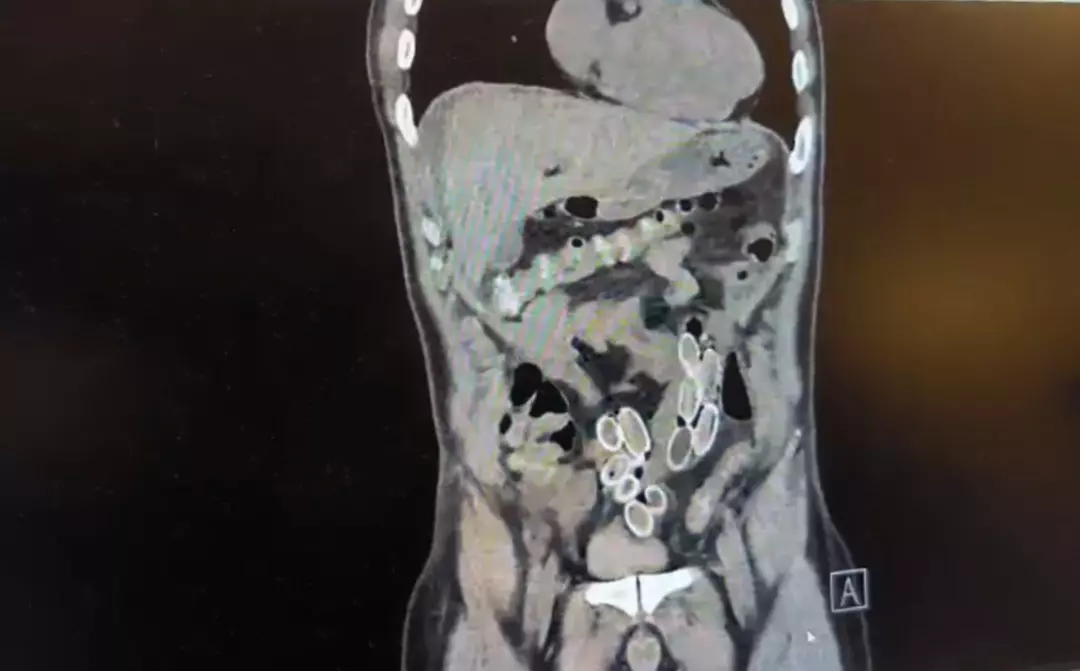

Tomografisi çekilen Cüneyt Ç.’nin mide ve bağırsaklarında yabancı madde bulunduğu tespit edildi. Hastane yetkililerinin bilgi vermesi üzerine Beşiktaş Asayiş Büro Amirliği ekipleri tarafından konuyla ilgili çalışma başlatıldı. Ameliyata alınan Cüneyt G.’nin mide ve bağırsaklarından kapsül halinde 49 adet esrar macunu çıkarıldı.

Fas’tan yaklaşık 3 bin kilometre uzaklıktan uçakla Türkiye’ye gelen Cüneyt G., 2 gün sonra karın ağrısı şikayetiyle Fulya’daki özel bir hastaneye başvurdu. Yapılan muayenenin ardından Cüneyt G.’nin tomografisi çekildi. Şüphelinin mide ve bağırsaklarında yabancı madde tespit edilmesi üzerine hastane yetkilileri durumu polis ekiplerine bildirdi.

Doktorların değerlendirmesi sonrası ameliyata alınan Cüneyt Ç.’nin bağırsaklarından, toplam ağırlığı 259,7 gram olduğu öğrenilen 49 esrar macunu çıkarıldı. Şüpheliye ait 1 adet cep telefonu da hastane yetkilileri tarafından polis ekiplerine teslim edildi.